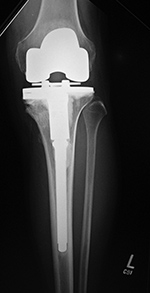

Limb sparing (salvage) prosthesis Varus-valgus lower limb salvage prosthesis (limb-salvage total knee arthroplasty)

Limb sparing prosthesis Limb sparing prosthesis lateral view Lower limb salvage prosthesis Lower limb salvage prosthesis

17 year-old woman with Ewing sarcoma treated with limb sparing prosthesis This is a custom made prosthesis for a patient who was treated for a Ewing sarcoma. From Taljanovic, 2005